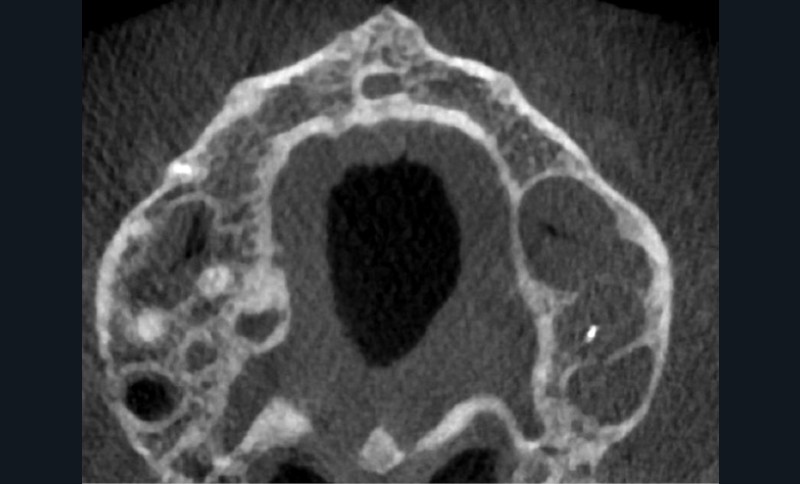

Endal, en 2011, montrait également, en utilisant le micro CT Scanner, l’insuffisance de nettoyage des isthmes inter-canalaires à nos techniques conventionnelles [19]. L’utilisation du laser Er:YAG devenait alors incontournable dans le nettoyage de ces isthmes et des zones non instrumentées (fig. 2 et 3).

Cette pénétration s’étend de la chambre pulpaire au réseau canalaire, isthmes, deltas apicaux et tubulis dentinaires. Il a été démontré que l’effet de cavitation pourrait permettre la destruction des bactéries à des profondeurs de 300 à 400 µm au sein des surfaces irradiées [20].

Si l’étude de Peters [18] nous montre que l’instrumentation laisse 35 % du volume canalaire non instrumenté, Ricucci et Siqueira montrent que la préparation physico-chimique n’élimine que partiellement les tissus nécrotiques à l’entrée des canaux latéraux, des isthmes et des ramifications apicales, en laissant des tissus enflammés et infectés, en association avec des lésions apicales [29] (fig. 4 et 5).

Fig. 4 – Coupe d’une racine mésiale de molaire mandibulaire avec deux canaux traités. Coupe à 3 mm de l’apex, coloration Brown et Brenn, technique modifiée par Taylor. Ces images montrent un isthme étroit avec une infection bactérienne, ce qui prouve l’importance de désinfecter et d’inclure l’isthme dans les traitements conventionnels et dans les rétropréparations apicales en chirurgie endodontique.